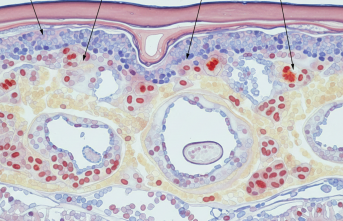

Tenin Kırılgan Hikayesi: Epidermolizis Bülloza